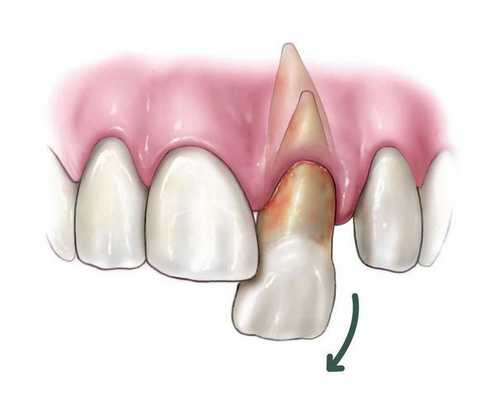

Вывих зуба подразумевает такой вид травмы, при которой зуб частично или полностью утрачивает связь с лункой. Неполный вывих зуба (экструзия) возникает в результате надрыва или разрыва периодонтальных волокон и повреждения стенки альвеолы. Данная разновидность травмы характеризуется болью, подвижностью и изменением положения зуба, нарушением функции жевания. Коронка зуба при неполном вывихе смещается в вестибулярном, оральном, дистальном или других направлениях, а корень зуба - в противоположную сторону. Вследствие нарушения целостности тканей периодонта могут образовываться патологические, кровоточащие зубо-десневые карманы. Неполные вывихи зубов могут осложняться образованием зубных гранулем и корневых кист, хроническим периодонтитом, нарушением развития корня зуба, расширением или облитерацией зубных каналов.

Неполный вывих характеризуется сохранением зуба в его лунке и сопровождается разрывом части волокнистых структур, окружающих и удерживающих зуб, либо растяжением волокон в той или иной степени. Для данной патологии характерно изменение положения коронки зуба и корня в зубном ряду по отношению к стенкам альвеолы. Зуб имеет неправильное положение вследствие смещения в вестибулярную ( в сторону губы) или оральную сторону, в сторону соседнего зуба или поворота вокруг оси. Это приводит к нарушению формы зубного ряда. Неполный вывих может сочетаться с переломом коронки, корня зуба или альвеолярного отростка.